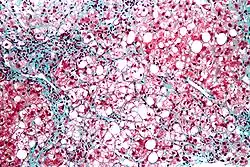

![]() | |

| Micrograph showing a fatty liver (macrovesicular steatosis), as seen in metabolic dysfunction–associated steatotic liver disease. Trichrome stain. | |

The fatty change represents the intracytoplasmatic accumulation of triglycerides (neutral fats). At the beginning, the hepatocytes present small fat vacuoles (liposomes) around the nucleus (microvesicular fatty change). In this stage, liver cells are filled with multiple fat droplets that do not displace the centrally located nucleus. In the late stages, the size of the vacuoles increases, pushing the nucleus to the periphery of the cell, giving a characteristic signet ring appearance (macrovesicular fatty change). These vesicles are well-delineated and optically "empty" because fats dissolve during tissue processing. Large vacuoles may coalesce and produce fatty cysts, which are irreversible lesions. Macrovesicular steatosis is the most common form and is typically associated with alcohol, diabetes, obesity, and corticosteroids. Acute fatty liver of pregnancy and Reye's syndrome are examples of severe liver disease caused by microvesicular fatty change.[19] The diagnosis of steatosis is made when fat in the liver exceeds 5–10% by weight.[13][20][21]